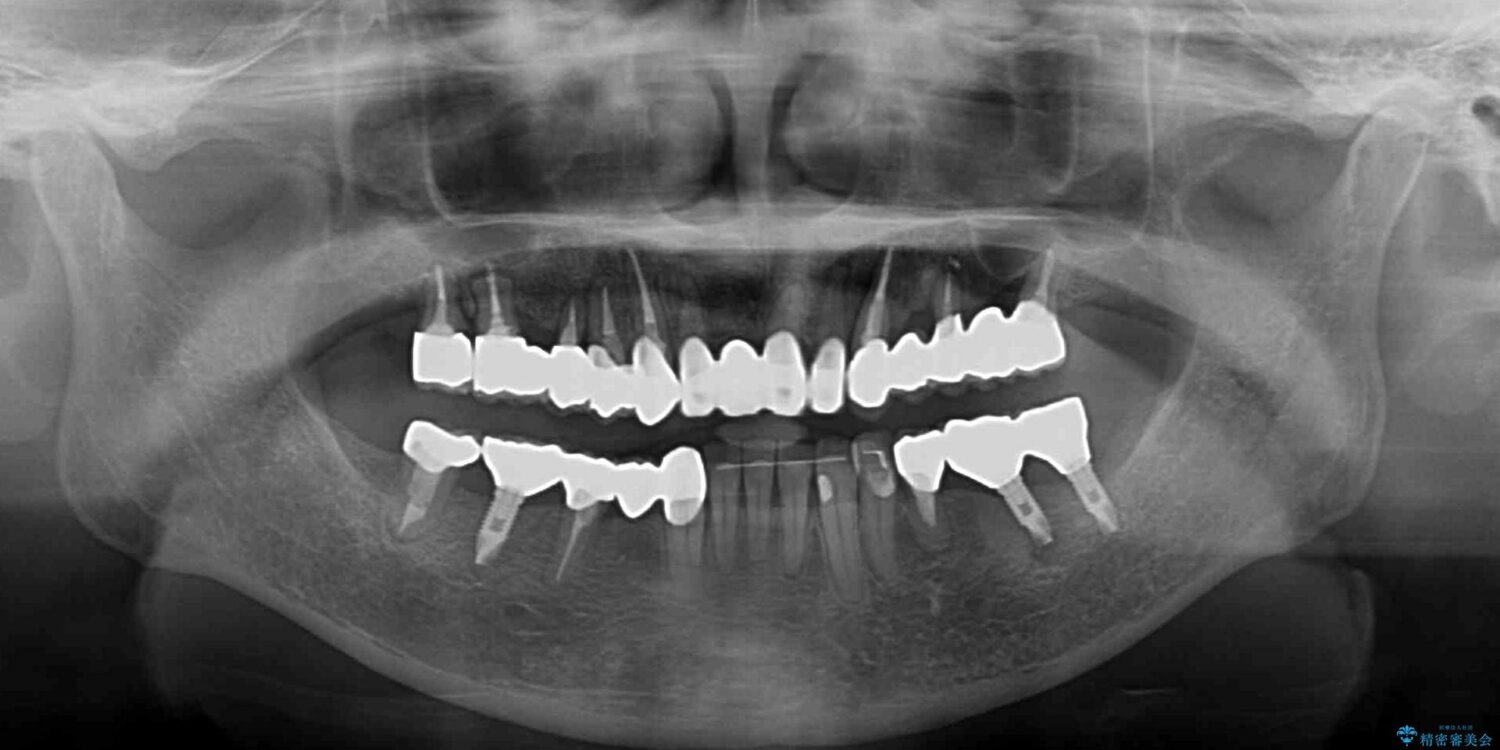

ご主人が当院に通院されていたことで、ご紹介により来院されました。 以前通院していた医院で、奥歯のインプラント埋入、前歯部のインビザライン矯正を行ったものの、そのまま放置してしまったとのことで来院された患者様です。

治療計画

下顎前歯や上顎奥歯などをワイヤー装置により部分矯正を行い、歯列を整えた上でインプラント部分を含めてオールセラミッククラウンにて補綴治療を行うこととしました。

治療後について

インプラント上の仮歯がボロボロになり、前歯に非常に負担のかかる状態であったため、早急に奥歯の仮歯を修復し、矯正治療、奥歯の補綴治療、前歯の補綴治療と順々に進めて行きました。